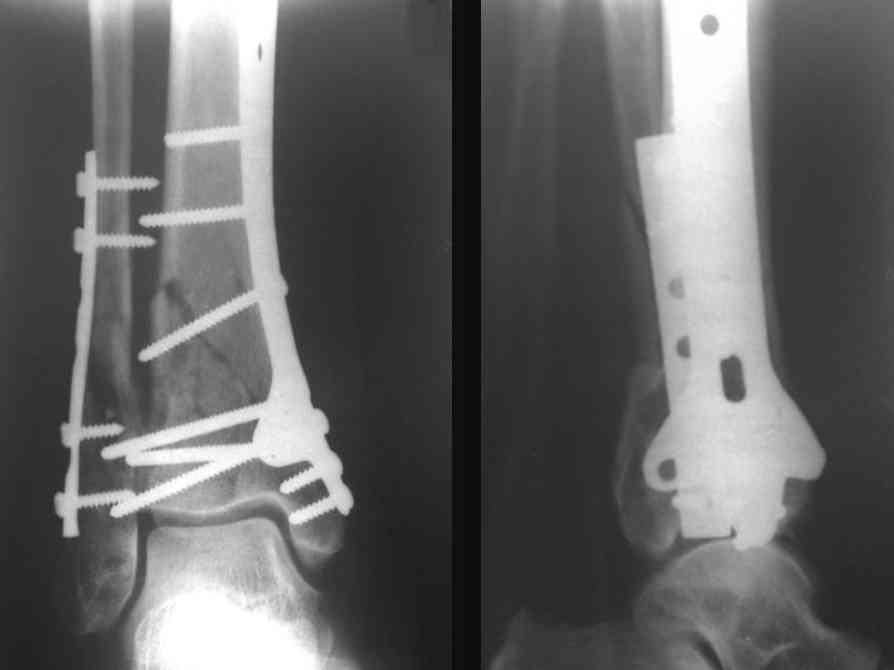

Это типичный перелом пилона, который надп лечить только открыто.Извини те что опоздал к обсуждению, но даже если вы уже оперировали больного по Илизарову это даже лучше.Посылаю картинки.

Посмотрим вроде прошло если понравится напишите расскажу как это сделать.По принципам АО кстати при поступлении сначала восстанавливают длину малоберцовой кости фиксируют пластиной 1/3 трубки потом накладывают аппарат наружной фиксации и через 7-10 дней открыто восстанавливают большеберцовую кость.С уважением Дрягин

На рентгенограммах типичный перелом пилона по типу С-3. есть опыт до 100 открытых опреаций у нас в клинике. 20 примерно в год. Принцип один -все внутрисуставные переломы нуждаются в открытой репозиции и внутренней стабильной фиксации. При поступлении КТ не надо, так как получается только нагромождение костей. Истинной картины нет. Главное восстановить длину малоберцовой кости - это ключ к успеху. При поступлении меньше всего надо думать о сосудистых расстройствах, т.к. сама операция и репозиция даже сначала частичная даёт улучшение сосудитых нарушений. Причём очень быстро. Операция в 2этапа. При поступлении доступ позади наружной лодыжки, причём обязательно. После этого репозиция малоберцовой кости и фиксация пластиной 1/3 трубки под винт 3,5. Дренаж и любой аппарат наружной фиксации. Затем после спадения отёка на 5-7-10 день аппрат снимается и дугообразный разрез спереди от медиальной лодыжки 10-12 см. Главной чтобы расстояние между 1 и вторым разрезом было не меньше 7-8 см. Тогда не будет некрозов лоскутов. Таранная кость используется как матрица на неё укладываются отломки и фиксируются пицами. Ренг-контроль. Отломки лежат все отдельно, но ничего не высыпется. При переломах С-3 всегда нужна костная пластика (из крыла). Фиксация пластиной лист клевера простой или LCP. Гипс не нужен. Дренаж до 48 часов. Операция длится 3-4 часа обязательно без жгута. Посылаю примерно такой же случай.

Послала ещё два снимка, если не пройдут, пошлю ещё. Дрягин. Если есть вопросы, готов ответить.